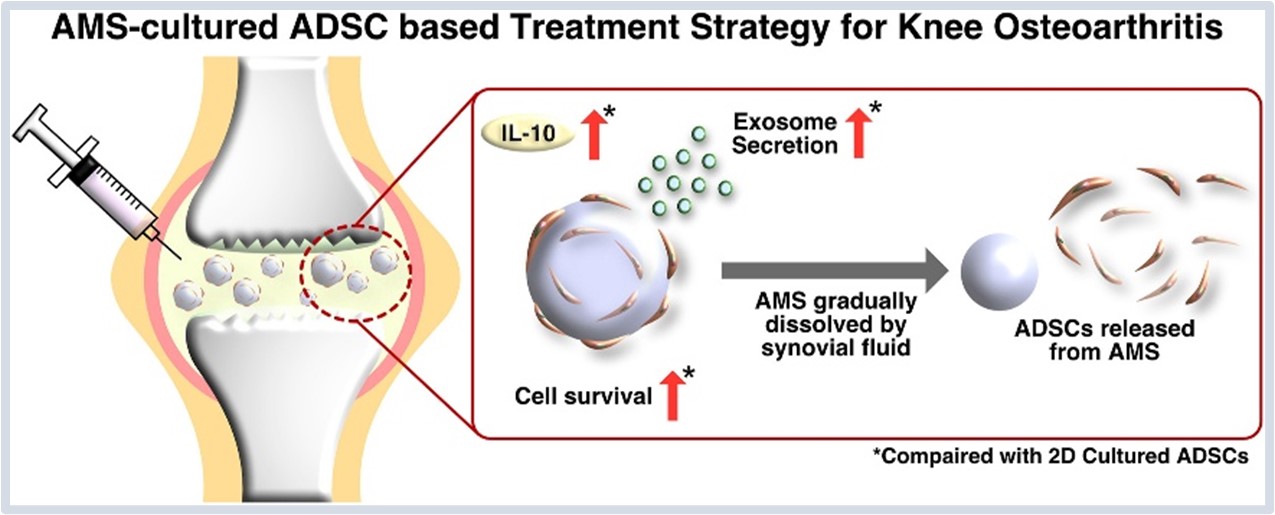

细胞~ 24小时预测改善退化性关节炎关节炎模型

膝关节健康关键在于软骨细胞的正常结构。健康的软骨细胞多为圆形或椭圆形,规则地分布于由胶原与聚糖组成的基质网络中,协同维持关节的运动功能。而在退化性关节炎(OA)中,软骨细胞出现形态异常、数量减少,基质代谢失衡,导致软骨功能逐步丧失。